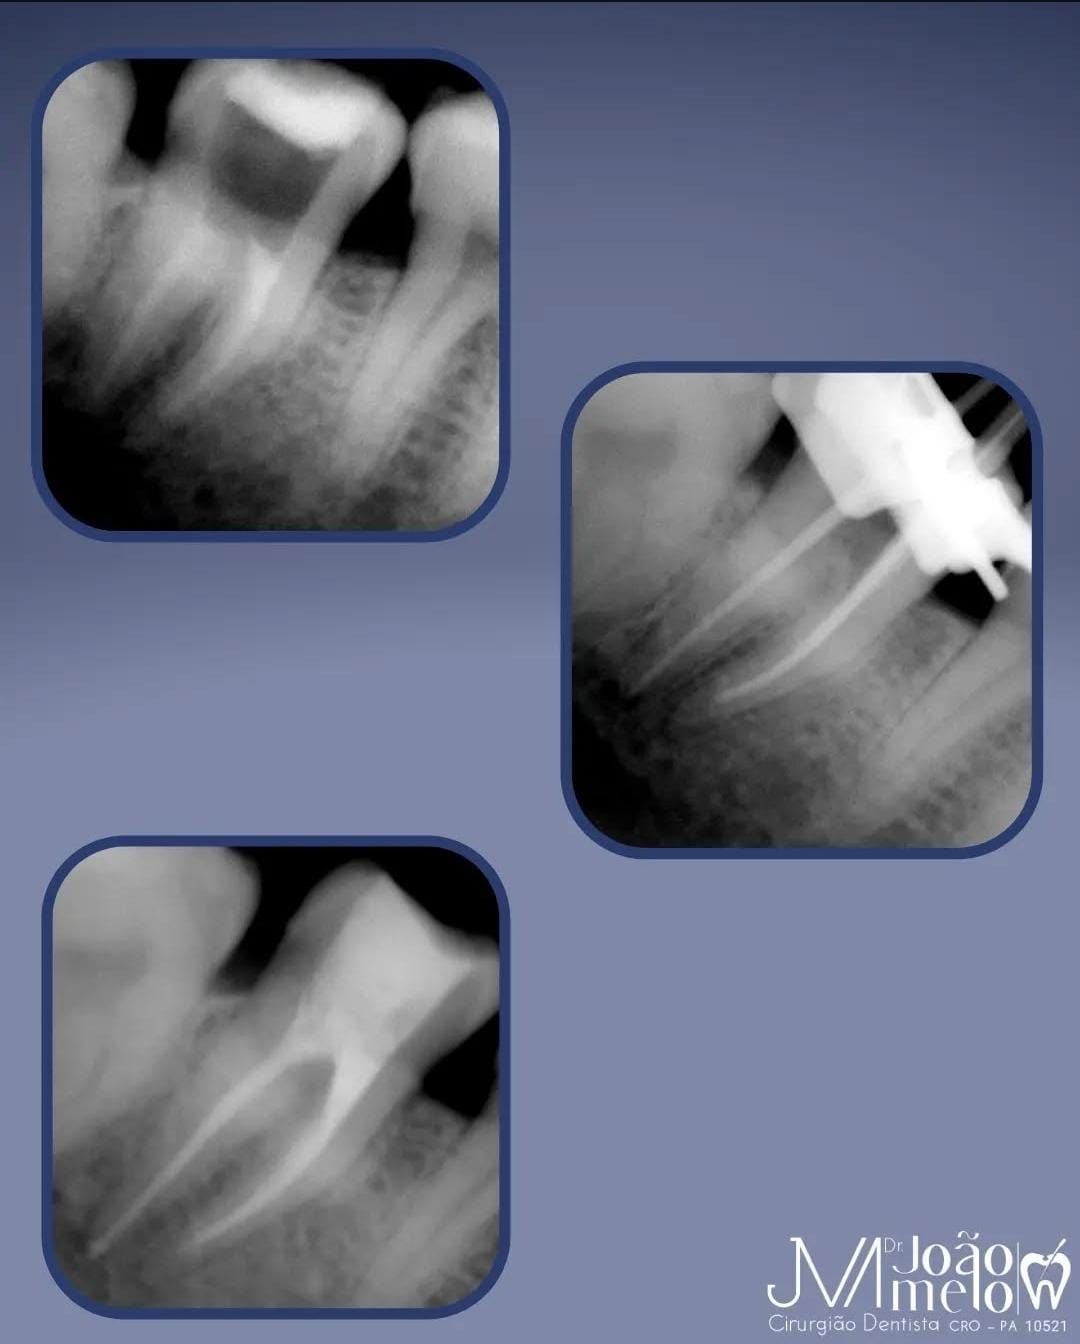

Especialidade principal. Remoção da polpa inflamada para alívio imediato da dor e preservação do dente.